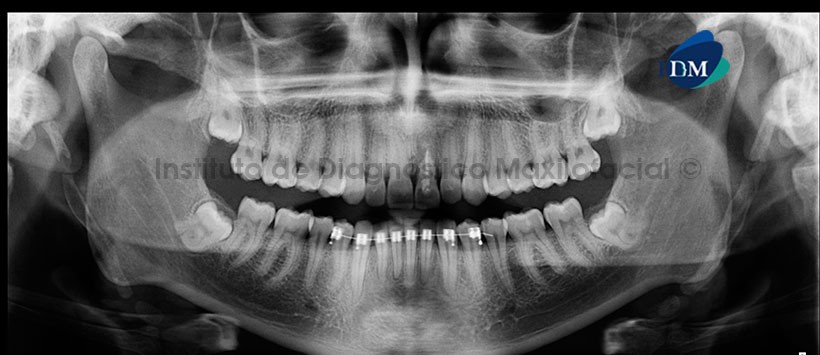

Paciente masculino de 27 años de edad acude al Instituto de Diagnóstico Maxilofacial por evaluación de terceras molares. Motivo por el cual se le realiza un estudio imagenológico.

A la evaluación de la radiografía panorámica se observa que el paciente presenta aparatología fija para ortodoncia en sector dentario anteroinferior, las piezas 18 y 28 están retenidas, las piezas 38 y 48 impactadas en posición mesioanguladas, la pieza 21 presenta disminución de la longitud radicular, así como la presencia de material de obturación. Sin embargo, lo más resaltante es la presencia de formaciones radiopacas que se extienden desde la base del cráneo, en dirección caudal hacia la línea media; proyectadas sobre ambas ramas mandibulares compatible con tejido blando mineralizado. (Figura 1).